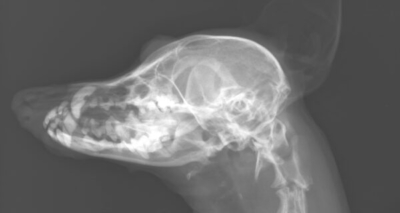

基礎疾患がありシニアの子ではありましたが、歯周病は経過観察しても治るというものではありません。別日に全身麻酔下で歯科レントゲン、口腔内精査を行い歯石除去、抜歯などを検討しました。術前検査の頭部レントゲン検査では、上顎犬歯に欠損があることもわかりました。こちらも手術中に確認することとしました。

頭部レントゲン

先ほどの頭部の拡大図。黄色矢印の位置で犬歯に一部虫歯のような欠損部が。